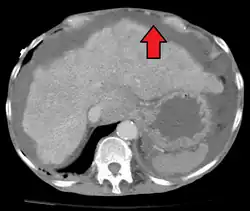

Liver cirrhosis with ascites

Ultrasound investigation is often done before attempts to remove fluid from the abdomen. This may reveal the size and shape of the abdominal organs, and Doppler studies may show the direction of flow in the portal vein, as well as detecting Budd–Chiari syndrome (thrombosis of the hepatic vein) and portal vein thrombosis. The sonographer also can estimate the amount of ascitic fluid, and difficult-to-drain ascites may be drained under ultrasound guidance. An abdominal CT scan is more accurate than a sonogram to reveal abdominal organ structure and morphology.[13]